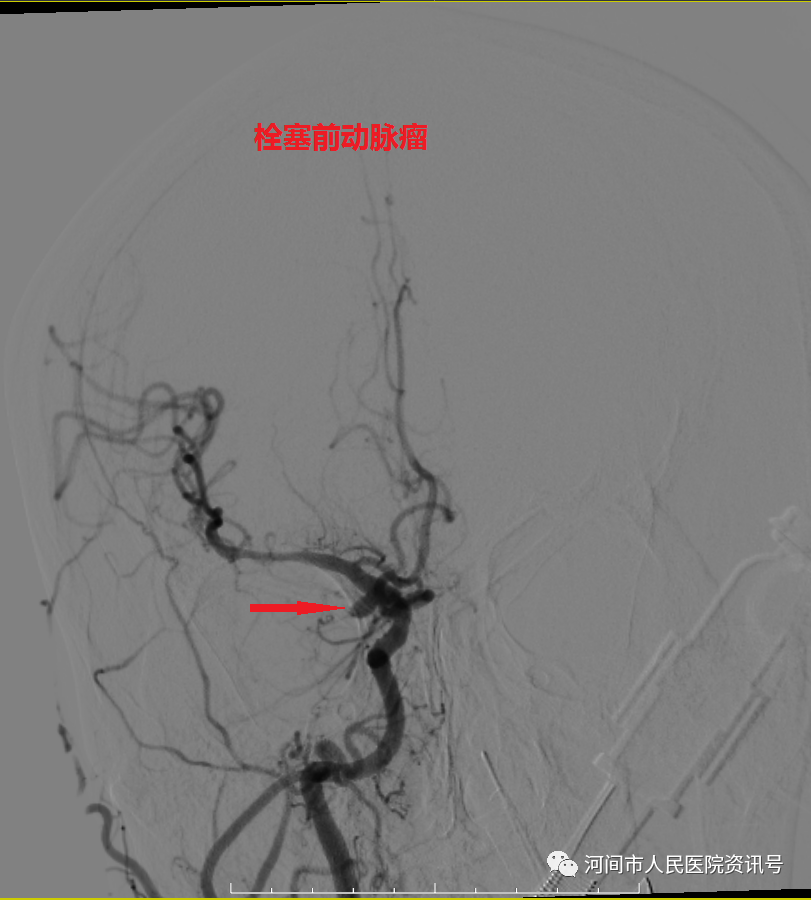

急诊立即开通绿色通道收入神经内三科。神经内三科吴俐欣主任紧急完善头颈CTA,报告显示右侧颈内动脉C7段动脉瘤,长径约5.5mm,同时头颅CT示患者颅内出血较前明显增加。患者突然意识不清、处于昏迷状态,继而呼吸骤停。紧急情况下,立即给予患者气管插管,随后转入重症监护室继续治疗。经神经内三科、ICU、神经外科等多科通力协作,于4月2日15时20分,神经内三科副主任杜文辉、医师刘建伟在介入科、麻醉科配合下,为患者成功施行了“全脑血管造影术+颅内动脉瘤栓塞术”,神经外科医师对患者进行了脑室外引流术,及时挽救了患者生命。在医护团队的精心照料下,目前,患者意识清醒,言语流利,四肢活动自如。

栓塞前图片